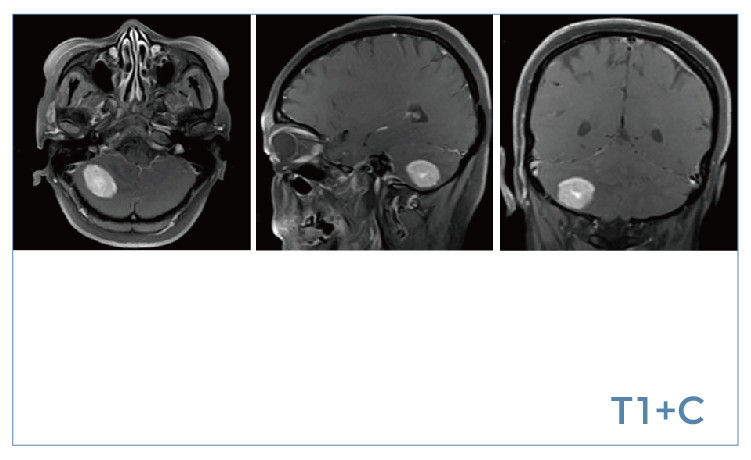

【朗润影像档案】20190802磁共振影像病例结果讨论